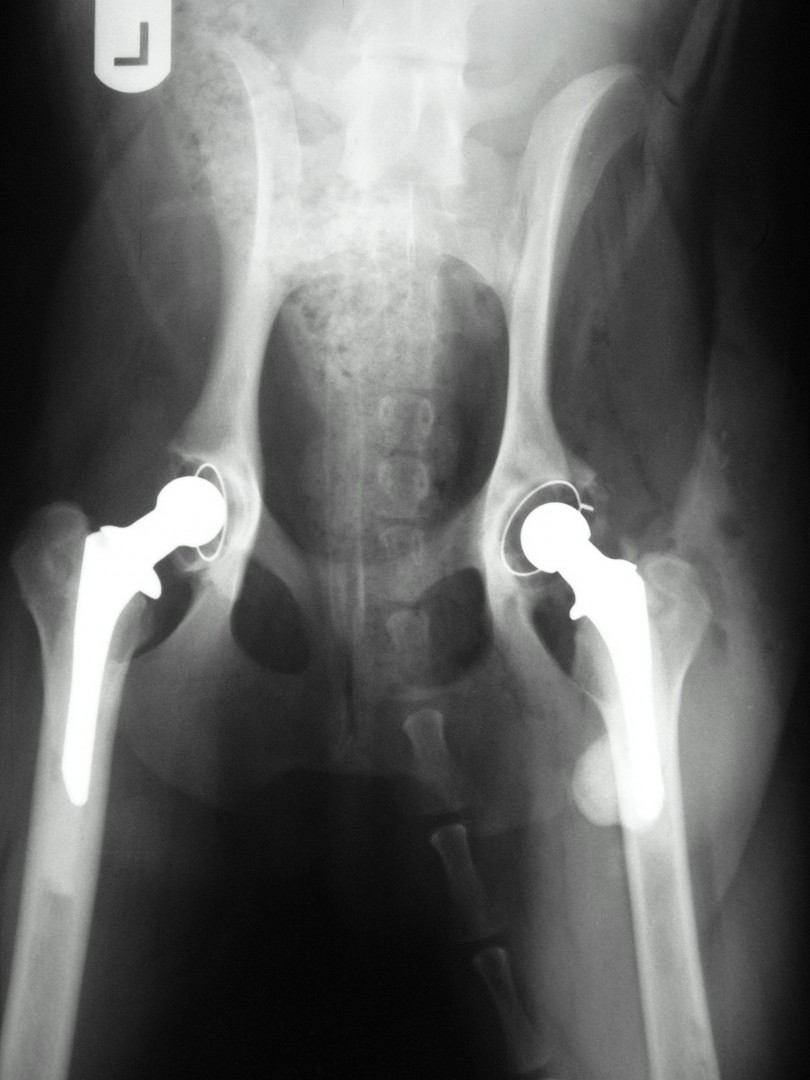

Teljes csípőízületi protézis

Az első műtét remekül sikerült és Connor, a skót juhász kutya megkapta a bal oldali új csípőízületét. A 7 napi kórházi tartás is problémamentesen zajlott és a varratszedés idejére a műtött végtag terhelése gyakorlatilag hibátlan volt. Az 1 hónapos és a 3 hónapos kontroll RTG vizsgálatokon sem jelentkezett szövődményre utaló jel, az 1 éves postoperatív időszakban már csak az látszott, hogy a műtött lábát jobban terheli, mint a nem operált végtagot. Így 2011. júniusában – immár sokadik csípőízületi protézis műtétként- a jobb oldali csípőízületét is megoperáltuk. Connor gyakorlatilag azóta teljes életet él és vidáman játszik társaival, még birkákat is terel…A majd két éves, a protetizálás során szerzett tapasztalatok azonban nálunk is hozzák a szakirodalomban leírt szövődményi lehetőségeket és arányokat. Leggyakrabban a beültetett protézis ficamával találkoztunk, de akadt sajnos kilökődési reakció is. Ezen problémák – az előzetes tájékoztatás ellenére is- mindig váratlanul érik a tulajdonost és az állatorvost egyaránt. Megoldásuk szinte kizárólag műtéti, ami újabb kockázatot, újabb fizikai és anyagi áldozatot jelent.